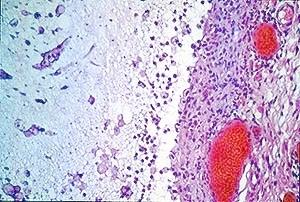

Atlas of skin histopathology

Mucus Retention =الأحتباس المخاطي